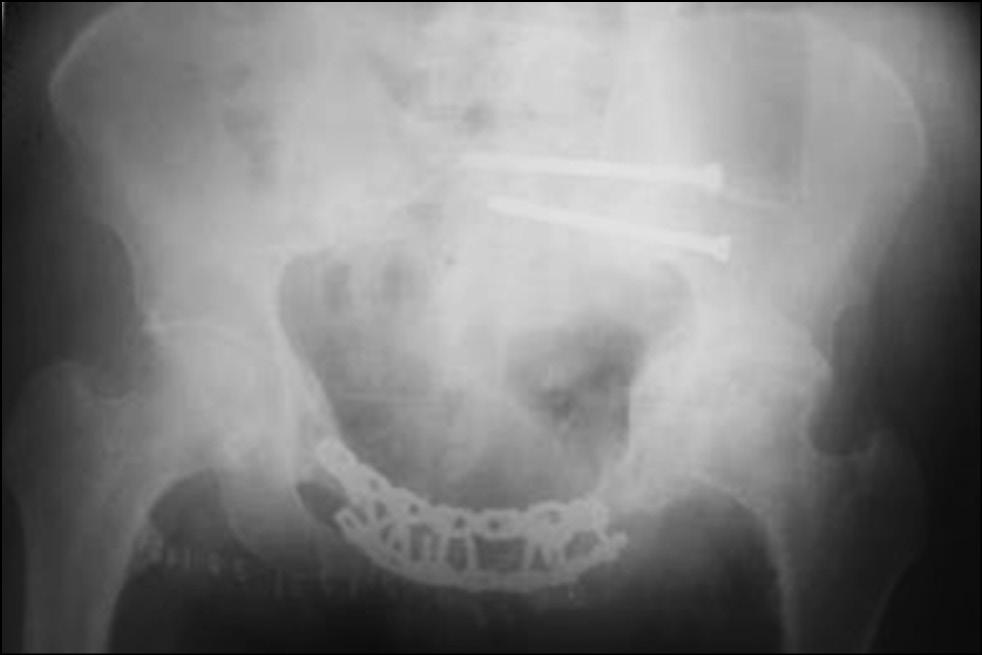

После низведения левой половины таза на втором этапе нами выполнен металлодез переднего полукольца таза двумя реконструктивными пластинами и произведена фиксация левого крестцово-подвздошного сочленения двумя канюлированными винтами (рис. 7, 8).

Рис. 7. Обзорная рентгенография таза после операции

Fig. 7. Plain radiography of the pelvis after surgery

Рис. 8. Каудальная рентгенография таза. Проекция in-let

Fig. 8. Caudal radiography of the pelvis. In-let projection